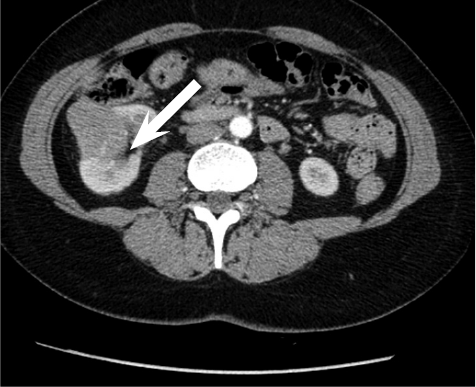

A 52 year old woman arrived at a hospital for a routine health check-up. Abdominal ultrasound revealed a 4.5 cm diameter lesion in the right kidney. Patient was directed to perform a contrast-enhanced computed tomography (CT), which was performed to specify the nature of the formation. CT found 49 mm x 34 mm cyst in the middle-lower portion of right kidney with septum and contrast accumulation (Figure 1), it was classified as Bosniak III and partial nephrectomy was chosen as a main choice of treatment.

Figure 1. A contrast-enhanced Computed Tomography of abdomen was performed (a 49 mm x 34 mm cyst in the middle-lower portion of right kidney with septum and contrast accumulation was found (white arrow)